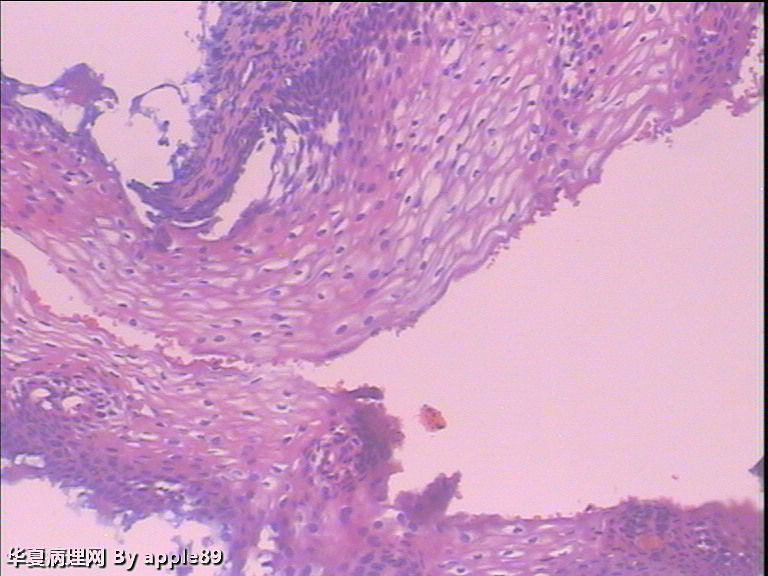

病人做阴道镜,没有看到明显醋酸白区域,随机活检了几块,由于组织受压变形,有点难看,不过补切之后,还是没发现啥问题。前两张是我从阴道镜报告上截的图,后几张是活检图

这个我也报的HSIL,但是活检结果挺郁闷……

临床用于白血病化疗的药物主要为烷化剂,这类药物可以引起宫颈的细胞学形态改变。药物常诱导人工绝经,引起的细胞学形态异常类似于LSIL或原位癌所见,此例的形态学改变为后者。

化疗对宫颈上皮的影响,与HPV感染有很大的相似性。6楼图4的组织学有点类似这种改变,在细胞学中化疗引起的改变常见的也为成熟的表层或浅表层细胞。楼主提供的病例以高核浆比细胞为主,也表明了化疗引起的细胞形态学改变是呈多样性的。希望能有更多的类似病例给我们学习。

本例部分异常细胞成团,胞浆稀少,但是由于部分异常细胞胞浆较丰富具有鳞状上皮的特点,所以可以排除白血病肿瘤细胞和腺上皮来源的异常细胞。

异常细胞核浆比增大,染色质增粗,染色深,核膜厚,但是核圆或卵圆,核膜光滑,如果我报,我是觉得报高级别是没有把握的。我还是觉得报“ASC=H,建议取活检”更好。这样我既没有排除高级别,但是也没有完全肯定,活检下来是高级别或不是高级别都不会太被动。